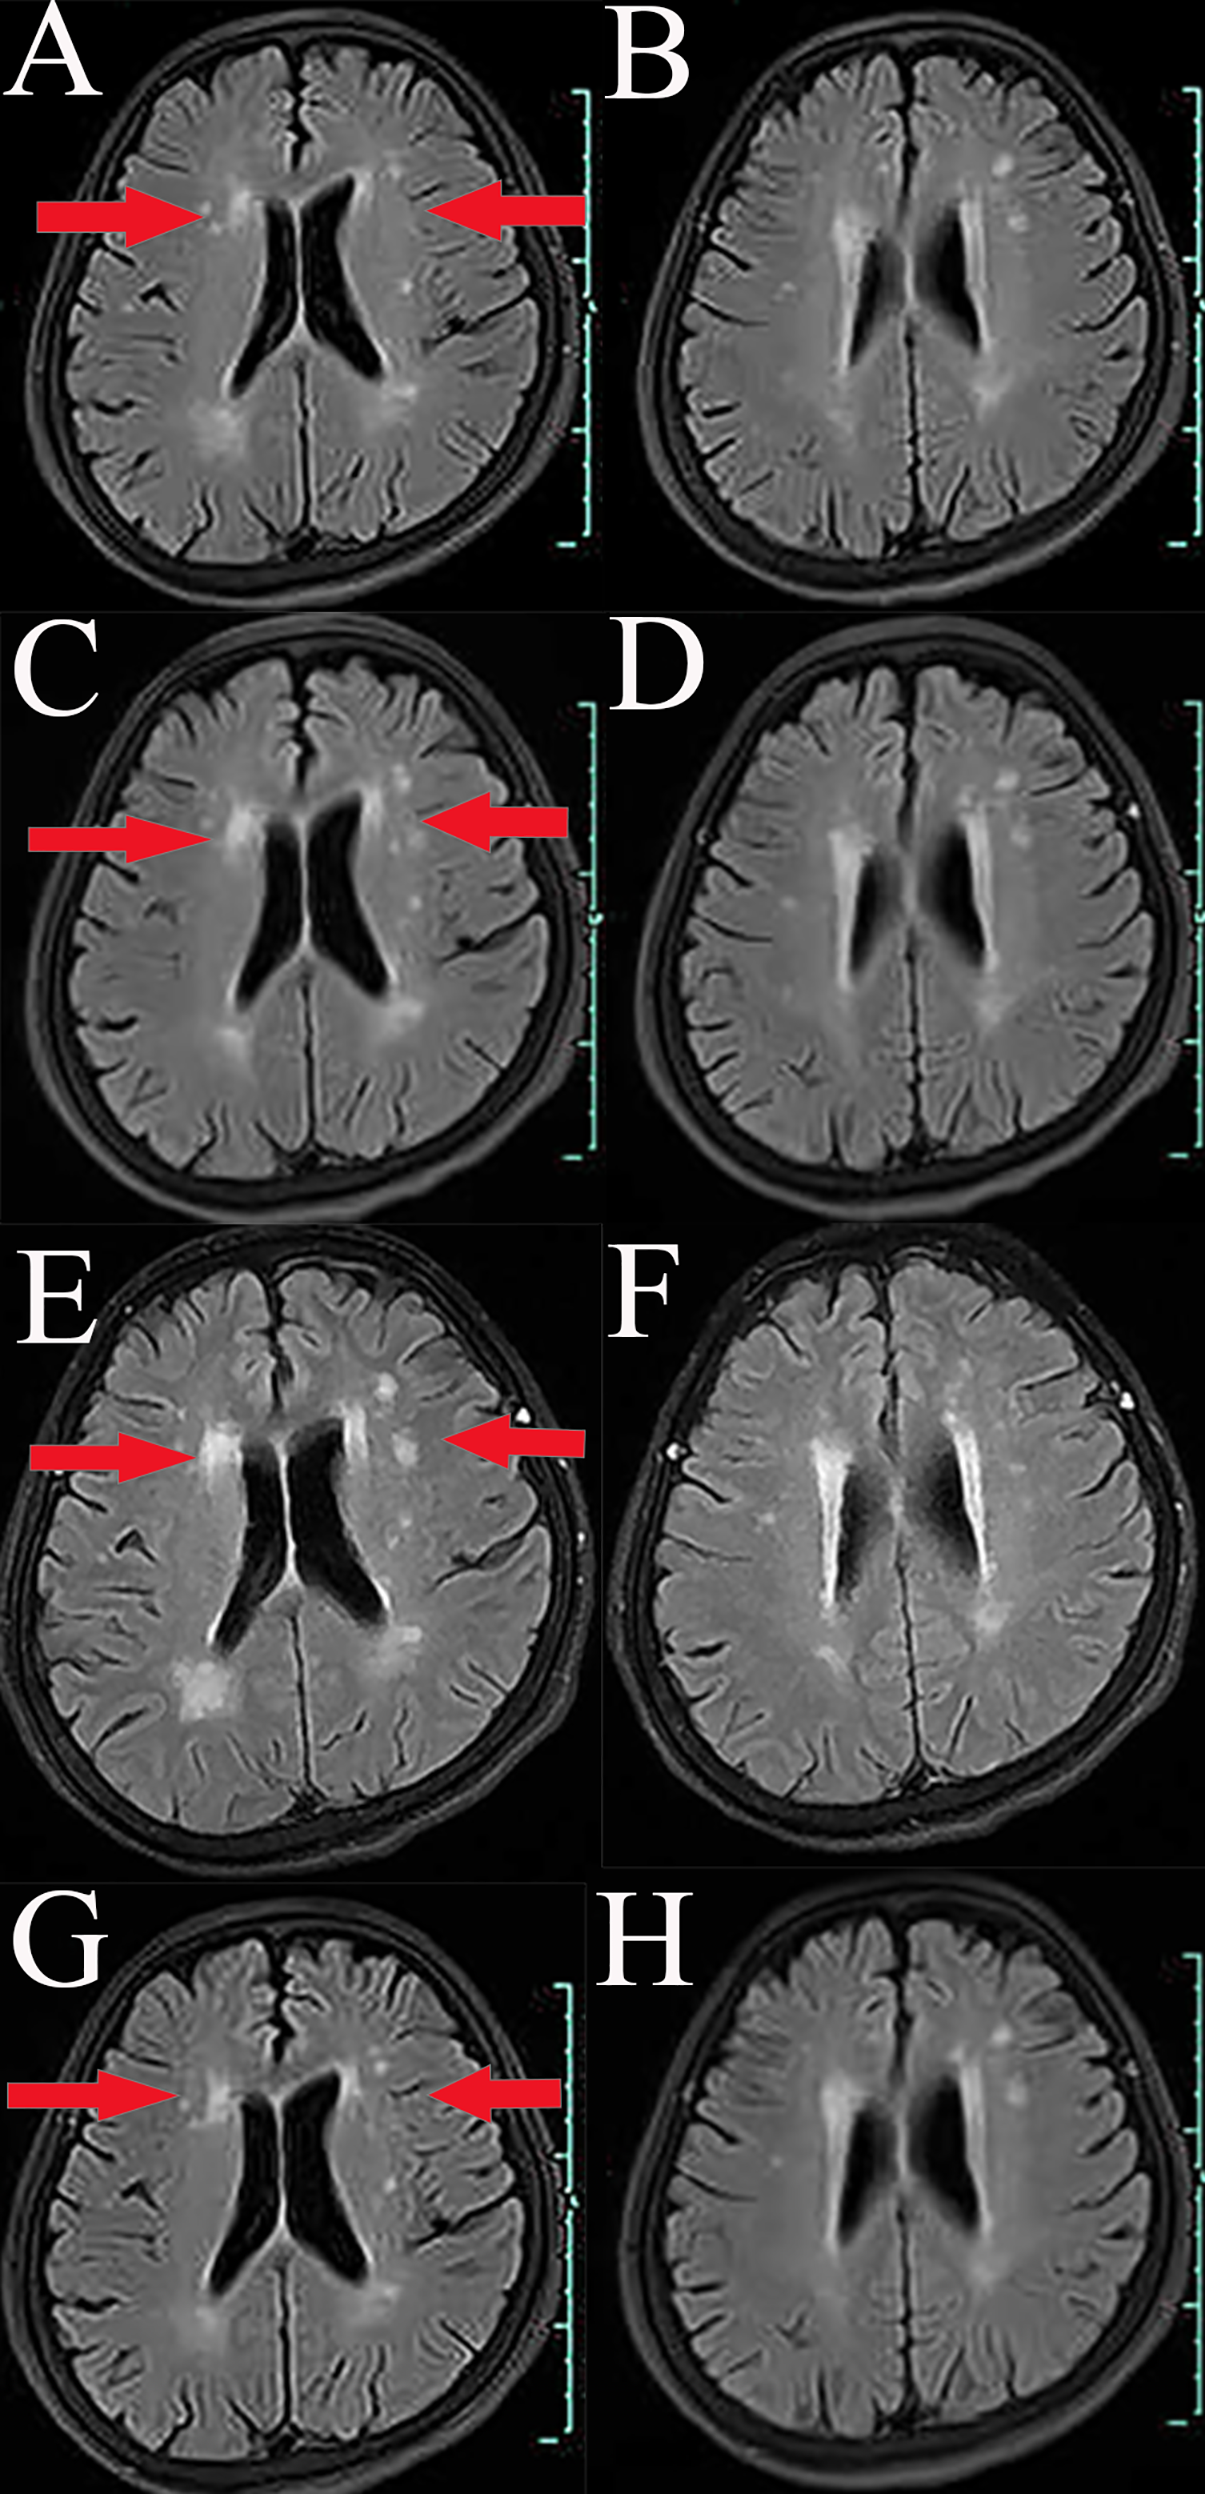

A 66-year-old Chinese woman was admitted to Quzhou People′s Hospital on February 18th, 2022 with a mild cough and sputum that had persisted for half a year. The patient denied any history of smoking, alcohol consumption, or any related medical or family history. Subsequent chest-enhanced computed tomography (CT) results revealed diffuse nodular shadows in both lungs, accompanied by multiple lymphadenopathies in the mediastinum (Figures 1A, B). A percutaneous lung biopsy was performed, and tissue samples obtained were subjected to immunohistochemical analysis, confirming a diagnosis of lung adenocarcinoma. An enhanced magnetic resonance imaging (MRI) of the head conducted on February 20th, 2022, demonstrated multiple spotty enhancement shadows in the brain (Figures 2A, B). Immunohistochemistry findings were as follows: CK7 (positive), CK20 (negative), CDX-2 (negative), TTF-1 (positive), Napsin A (positive); Ki-67 (positive, 5%), P40 (negative), SP-A (positive), S-100 (negative), and PD-L1 expression of <1%. Based on these results, a diagnosis of lung adenocarcinoma was made and staged as T4N2M1 according to the American Joint Committee on Cancer (AJCC) version 8th. The results of the Next-Generation Sequencing (NGS) test were not yet available when treatment decisions needed to be made. Considering the advanced stage of the disease, the patient was administered a regimen of pemetrexed 700mg and carboplatin 300 mg on February 25th, 2022. Subsequently, NGS did not identify any therapeutic targets, leading to the administration of five cycles of combined treatment with pembrolizumab (IV 240 mg on day 1, every 21 days), carboplatin (IV 400 mg on day 1, every 21 days), and pemetrexed (IV 700 mg on day 1, every 21 days), starting on March 18th, 2022. The patient then continued with 18 cycles of pembrolizumab (IV 240 mg on day 1, every 21 days) and pemetrexed (IV 700 mg on day 1, every 21 days) beginning July 1st, 2022. The brain MRI on February 21st, 2023 showed no progression (Figure 2C, D), and the chest CT on March 15th, 2023 showed that the mass was significantly smaller (Figure 1C, D). Due to the development of moderate facial edema on August 5th, 2023, we discontinued pemetrexed while continuing pembrolizumab for ten cycles. A follow-up chest CT (Figures 1E, F) and brain MRI (Figures 2E, F) on April 22nd, 2024, indicated that the tumor was slowly progressing. Subsequently, we performed NGS for the patient again, and the results showed the presence of a CD74-ROS1 fusion, with no variant allele frequency reported. The NGS assay employed was DNA-based and used a targeted panel covering 19 genes associated with lung cancer, including key oncogenic drivers such as EGFR, ALK, ROS1, and KRAS. Given brain metastases, we used entrectinib as a subsequent treatment at a dose of 600 mg per day (a potent oral multi-target TKI against ROS1, ALK, and NTRK-1, -2, and -3). According to the CT results on June 17th,2024, an efficacy assessment was performed and showed a partial response based on the Response Evaluation Criteria in Solid Tumors 1.1 criteria (Figures 1G, H). The brain metastases showed regression based on the June 17th, 2024 MRI (Figures 2G, H). Concurrently, notable reductions in the levels of tumor markers CEA and CA153 were observed during entrectinib therapy (Figures 3A, B). Presently, the patient remains stable and is willing to receive further treatment in our hospital (Figure 4).

Figure 2

Variations of occupation on brain areas by MRI images during the treatment (red arrowheads). (A, B), February, 2022. (C, D), February, 2023. (E, F), April, 2024. (G, H), July, 2024.